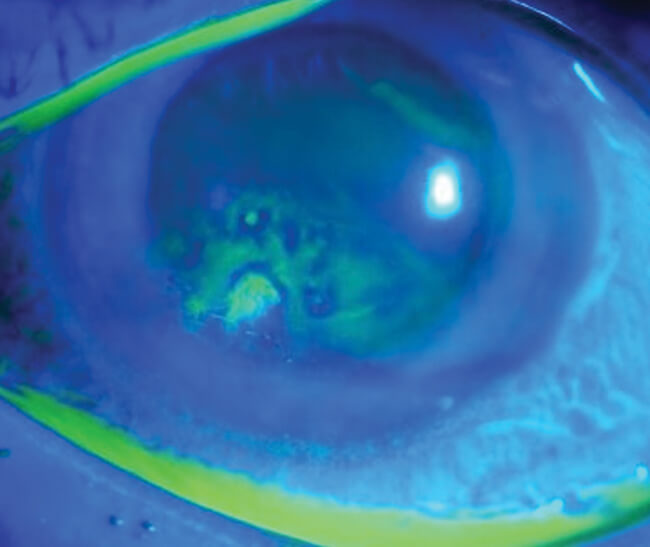

Recurrent corneal erosions secondary to isotretinoin use

This article originally appeared in Eye News Dec/Jan 2021 Isotretinoin (13–cis-retinoic acid) is the first line treatment for moderate to severe nodulocystic or papulopustular acne [1,2]. Although it is a safe medication, it has several adverse side-effects, including ophthalmic manifestations,...